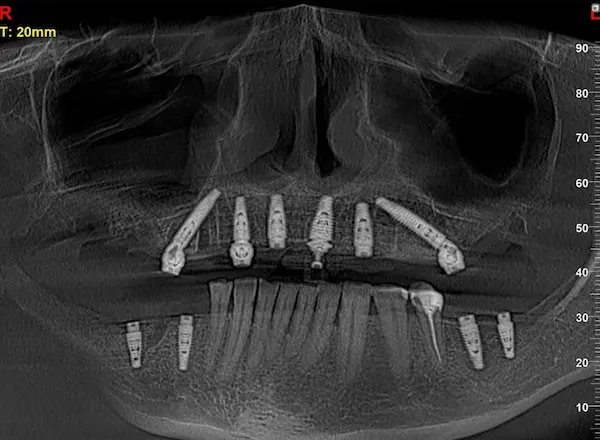

Сканы КТ имплантации зубов, 2026-04-18

Скан КТ, 2026-04-18

Сканы КТ имплантации зубов, 2026-04-18

Скан КТ имплантации зубов, 2026-04-17

Сканы КТ имплантации зубов, 2026-04-18

KT: имплантация зубов DentalKnysh, 2025-01-03, сканы

KT: имплантация зубов DentalKnysh, 2025-01-03, сканы

KT: имплантация зубов DentalKnysh, 2025-01-03, сканы

КТ имплантации зубов в DentalKnysh (10 имплантов), 2023-11-03

С 2023-09-05 по 2023-09-09 сканы КТ от 6 до 12 имплантов в DentalKnysh (4 фото):

Синуслифтинг и имплантация зубов, 6 имплантов, all-on-6, КТ скан 1, 2023-08-31

Фото отчет Имплантация зубов, 6 имплантов, КТ скан 3, 2023-08-31

Фото отчет Имплантация зубов, 8 имплантов, all-on-4, КТ скан 1, 2023-08-31